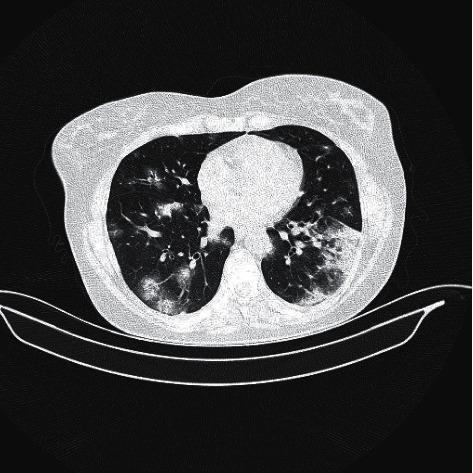

新型冠状病毒肺炎与重症肌无力并存:一例病例报告及文献综述

COVID-19 Presentation in Association with Myasthenia Gravis: A Case Report and Review of the Literature.

Currently, there are scarce data on how COVID-19 affects people with myasthenia gravis. Theoretically, there is a higher risk of experiencing severe manifestations of COVID-19 due to the common use of immunosuppressive drugs and potential respiratory failure in relation to respiratory muscle weakness. This is one of the early cases of COVID-19 reported in association with myasthenia gravis. Here, we highlight the prognosis, discuss the pathophysiological mechanisms, and prompt the consideration of convalescent plasma therapy in myasthenia gravis patients with concomitant COVID-19.

摘要